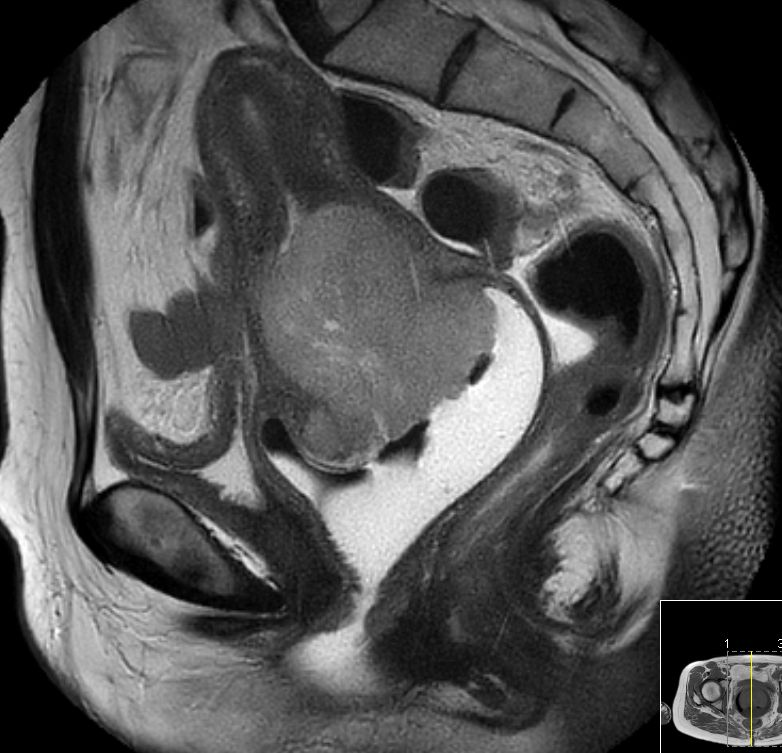

| MRT | 46-jährige Frau mit großem invasivem

Plattenepithelkarzinom der Zervix.![]() |

Im CT suspekter Lymphknoten iliaca externa links

neben der Blase.![]() | ||